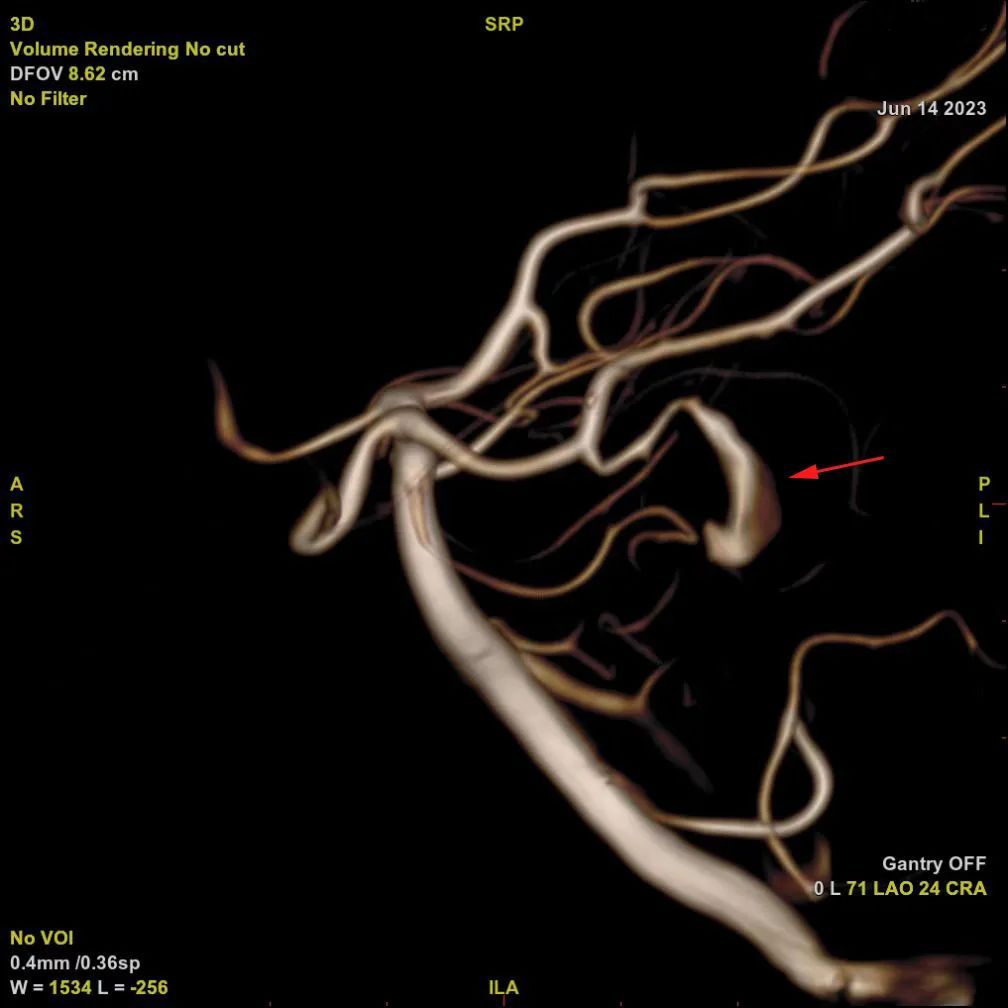

脑血管造影显示左侧大脑后动脉的细小分支上

有明显扩张延长(红色箭头处)

入院后,中山医院神经外科张晓彪主任带领脑血管病团队对其病情进行了深入地讨论,小马的脑血管造影结果进一步证实了团队的判断:左侧大脑后动脉一条大约1毫米直径的细小分支上有明显的扩张延长,考虑颅内夹层动脉瘤!此种病变容易引发脑内出血或脑栓塞,就像埋藏在大脑深处的一颗“不定时炸弹”,一旦爆炸,后果不堪设想。